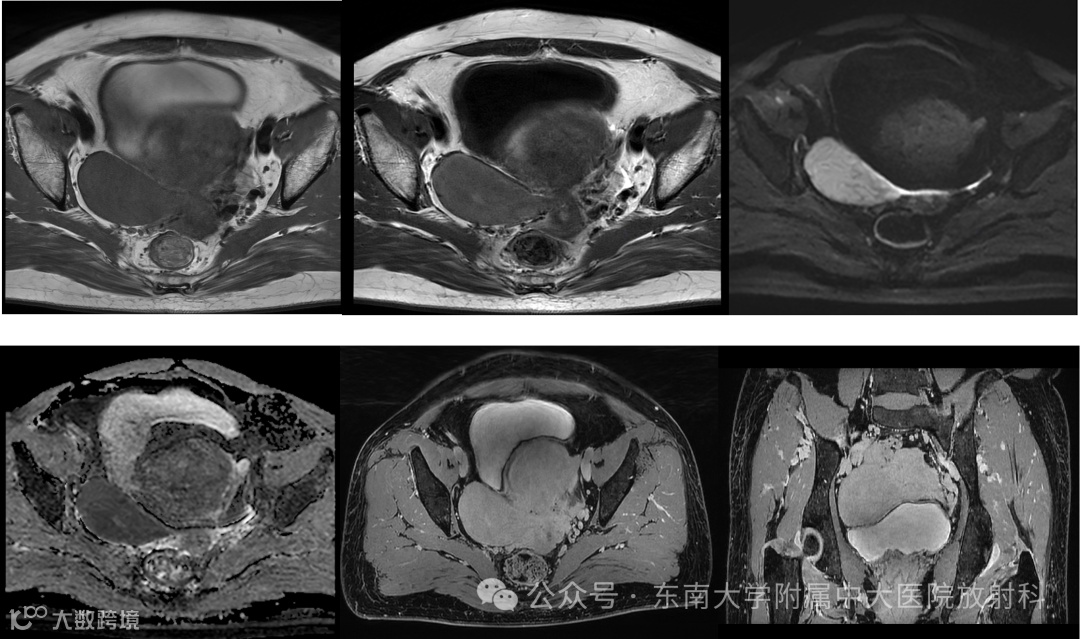

病例2

性别:女 年龄:53岁

主诉:检查发现右侧盆腔包块 5 年余

现病史:患者平素月经规律,量多,45岁时开始出现痛经,且进行性加重,遂至我院门诊,彩超提示右侧附件区低回声团,子宫增大,子宫腺肌症。门诊予行诊刮术,病理提示:子宫内膜增生紊乱伴嗜酸细胞化生。现患者为进一步诊治来我院,门诊拟“子宫腺肌病,右卵巢囊肿"收住入院

肿瘤指标:糖链抗原125:7.31U/ml,人附睾分泌蛋白4:32.30pmol/L

影像学表现